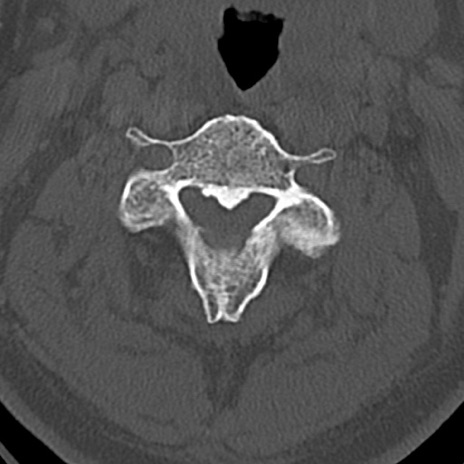

頚椎CT

横断像